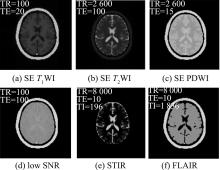

汪红志, 施群雁, 苗志英, 等. MRISim:磁共振成像仿真实验软件包[J]. 波谱学杂志, 2019, 36( 2): 225- 237.

|

Wang Hongzhi, Shi Qunyan, Miao Zhiying, et al. MRISim: A Software Package of Magnetic Resonance Imaging Simulator[J]. Chinese Journal of Magnetic Resonance, 2019, 36( 2): 225- 237.